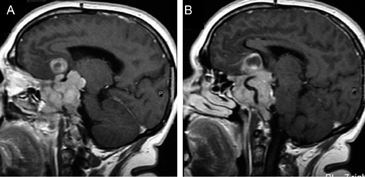

Figura 15 A, B y C. Cortes sagital T1w, coronal T1w Gad. y coronal T2w. Absceso pituitario que simula un macroadenoma quístico no funcionante.El compromiso del seno cavernoso (definido como la invasión perivascular de la arteria carotida interna), se observa en 19% de los macroadenomas y es habitualmente unilateral (Figuras 16A, 16B y 16C) pero puede ser bilateral en macroadenomas invasores (Figuras 17A y 17B). Para evaluar la invasión del seno cavernoso se utilizan las imágenes coronales T1w con gadolinio, efectuando el análisis de la forma y compartimientos del seno cavernoso y su relación con el adenoma; cuando el porcentaje de tumor que rodea la arteria carótida interna intracavernosa es mayor o igual a 66% del círculo medido alrededor de la carótida, hay invasión del seno, si es menor de 25%, el seno no está invadido48.

Figura 17A y B. Cortes coronal y axial transversal, T1w Gad. Macroadenoma con crecimiento hacia lateral (entre puntas de flecha), mayor a derecha con invasión de ambos senos cavernosos; el quiasma está libre.Los adenomas invasores (Figuras 18 y 19) constituyen un grupo aparte y de acuerdo con series recientes publicadas representan entre 10% a 35% de los adenomas pituitarios operados49. En estos casos el potencial de invasión es estimado con mayor precisión con estudios histoquímicos y ultraestructurales de las muestras obtenidas durante la cirugía. Estos estudios patológicos, en conjunto con la cuantía de tumor residual demostrada con las neuroimágenes postoperatorias, definirán la conducta terapéutica a seguir.

Figura 18A y B. Cortes sagitales, secuencia T1Gad. Macroadenoma invasor que se extiende al seno esfenoidal, al clivus, crece en el espacio retroselar, ocupa la cisterna supraselar y se extiende a la región subfrontal.

Figura 19A y B. Cortes sagitales T1w antes y después de inyección de Gadolinio. El tumor (prolactinoma) crece hacia caudal, invade el seno esfenoidal y erosiona el clivus (puntas de flecha), dejando libre la cisterna quiasmática. Los adenomas pituitarios invasores tienen características histológicas benignas, los malignos (carcinomas pituitarios) constituyen sólo el 0,2-0,5% de todos los tumores pituitarios50 y generalmente son macroadenomas funcionantes recidivados,que se presentan con metástasis subaracnoideas, cerebrales o sistémicas (Figuras 20 A, 20B, 20C y 20D).